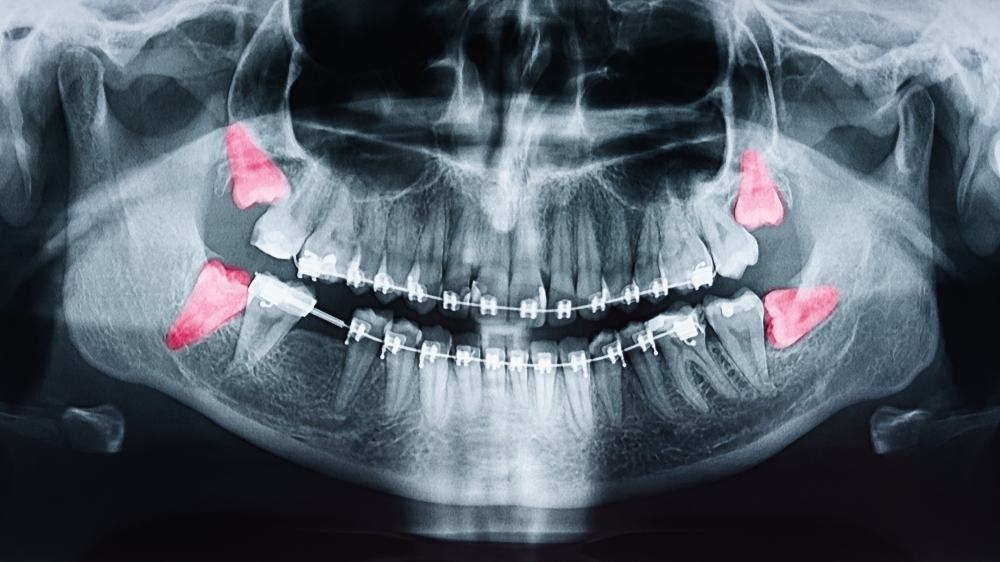

- Radiografia - zdjęcia rentgenowskie są niezwykle pomocne w diagnozowaniu chorób zębów i jamy ustnej. Pozwalają na wykrycie ubytków, stanu kości i korzeni zębów oraz innych zmian chorobowych.